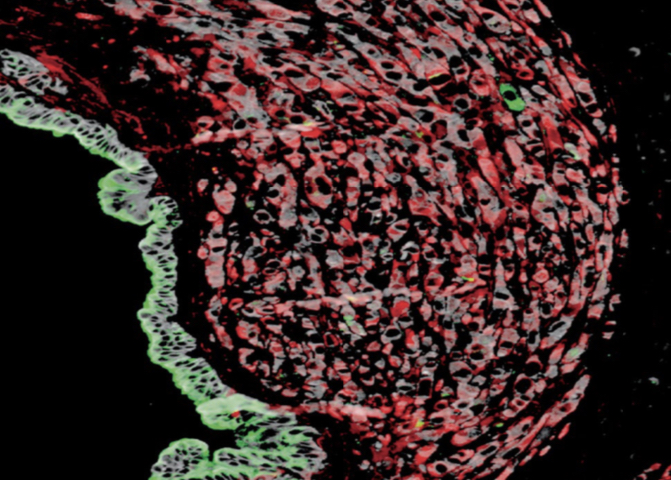

Working with our Human Organoid Facility and Biobank, the research team grew pancreatic organoids – a 3D in-vitro cellular model derived from patient samples designed to mimic a tumour environment. When the team switched off the gene that made SPP1, fewer tumours grew compared to when SPP1 was present.  Similar findings were also seen in mice with PDAC, where treatment with an antibody to block SPP1 significantly extended their survival with no cancer spread to other organs.